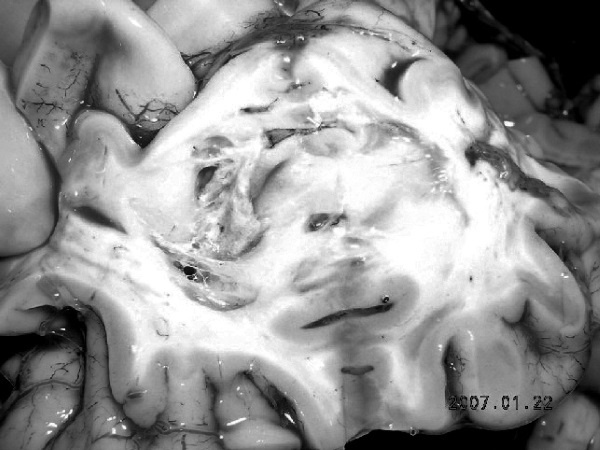

В посмертном эпикризе указан Основной диагноз: последствия ОНМК от 2008 года. ИБС. СН 2. ПИКС. Фоновое: СД 2-го типа, сопутствующее: хронический пиелонефрит. Осложнения: внебольничная пневмония. На секции: ![]() Рис. 31. Последствия перенесенного ОНМК ![]() Рис. 32. Атеросклероз церебральных артерий ![]() Рис. 33. Постинфарктный кардиосклероз ![]() Рис. 34. Гипертрофия миокарда левого желудочка ![]() Рис. 35. Признаки ХСН: мускатный фиброз печени ![]() Рис. 36. Пневмония ![]() Рис. 37. Признаки хронического пиелонефрита Анализируя данный клинический пример, необходимо отметить следующее. 1. Социальный статус. Социальный статус, за исключением указания на участие в ВОВ, не обозначен. 2. Наблюдение на дому. Полное несоблюдение регламента наблюдения ДИП. Клинический диагноз. Записи в амбулаторной карте нет. При этом диагноз должен быть следующим. Основной: последствия ОНМК от 2008 года. ИБС. Постинфарктный кардиосклероз. Фоновое: гипертоническая болезнь 3-й ст., 3 ст. риск 4. СД 2-го типа. Осложнения: длительная иммобилизация. Внебольничная пневмония. НК 2. Хронический пиелонефрит. Анемия. 3. Обоснованность назначения лекарственных препаратов. Терапия СД проводилась вне соответствия с клиническими рекомендациями, контроль за уровнем гликемии не осуществлялся, лечение анемии отсутствовало, вместе с тем при отсутствии подтвержденных данных за пиелонефрит были назначены антибиотики. Таким образом, наряду с указанными замечаниями врач не оценил тяжесть состояния, что не позволило решить вопрос о показанной госпитализации. Приложение № 6 – алгоритм лечения анемии. Приложение № 7 – самоконтроль уровня глюкозы. Пациентка Ф., 84 года. Умерла в январе 2011 года. Иммобилизирована с марта 2010 года в связи с закрытым переломом лонной и седалищной костей. В карте ежемесячные осмотры терапевта в связи с активами СМП. Причина вызовов: гипертонические кризы и болевой синдром. За год до смерти проведены доступные на дому анализы. В плановом порядке в апреле 2010 году проходила стационарное лечение в терапевтическом отделении. Диагноз при выписке: дисциркуляторная энцефалопатия 2-й ст. ГБ. ИБС. СН 3. ПИКС от 2001 года. Железодефицитная анемия. Закрытый перелом лонной и седалищной костей справа. Амбулаторно после стационара принимала энап Н и винпоцетин. В посмертном эпикризе указан Основной диагноз: 1) дисциркуляторная энцефалопатия 2-й ст. и ИБС. СН 3. ПИКС от 2001 г. НК 2А. Фоновое: ГБ. Сопутствующее: хроническая железодефицитная анемия. Закрытый перелом лонной и седалищной костей от 11.03.2010. ![]() Рис. 38. Повторный инфаркт головного мозга ![]() Рис. 39. Постинфарктный кардиосклероз ![]() Рис. 40. Атеросклероз коронарных артерий ![]() Рис. 41. Проявления НК: мускатный фиброз печени ![]() Рис. 42. Острые эрозии желудка ![]() Рис. 43. Атеросклероз аорты Замечания к ведению больного следующие: 1. Социальный статус. Информации нет. 2. Наблюдение на дому. Посещение терапевта осуществлялось только в связи с активами СМП. 3. Клинический диагноз. Нет правильной формулировки диагноза. При этом правильный диагноз был бы следующим. Основной диагноз: 1) Повторный инфаркт головного мозга. 2) ИБС. Постинфарктный кардиосклероз от 2001 года. Фоновое: гипертоническая болезнь 3 ст., 3 ст. Осложнения: закрытый перелом лонной и седалищной костей от 11.03.2010. Длительная иммобилизация. НК 2. Острые эрозии. Хроническая железодефицитная анемия. Сопутствующие: атеросклероз аорты. 4. Обоснованность назначения лекарственных препаратов: лекарственная монотерапия ГБ эналаприлом неэффективна, что повлекло за собой неоднократные гипертонические кризы и вызовы СМП, нет лечения проявлений ПИКС и анемии. Таким образом, не было оценки тяжести состояния, наличия тяжелой степени АГ у больной с перенесенным ОНМК и инфаркта миокарда, кризовым течением и признаками СН, что требовало госпитализации пациента. Приложение № 8 – ведение больного, перенесшего инфаркт миокарда. Пациентка Б., 95 лет. Иммобилизирована. Карта малоинформативна. Осмотры терапевта 1–2 раза в год, лист впервые выявленных диагнозов не ведется. Анализы отсутствуют. Известно, что наблюдалась с диагнозом ИБС, ЦВБ. Хронический бронхит. ОНМК с левосторонним гемипарезом и перелом шейки бедра без указания давности. В карте имеются указания на пролежни. За последние 2 года до смерти терапевтом были назначены: пирацетам, предуктал, мексидол, проведен курс ЛФК на дому. Посмертный эпикриз отсутствует. На секции: ![]() Рис. 44. Последствия перенесенного инфаркта головного мозга ![]() Рис. 45. Постинфарктный кардиосклероз |